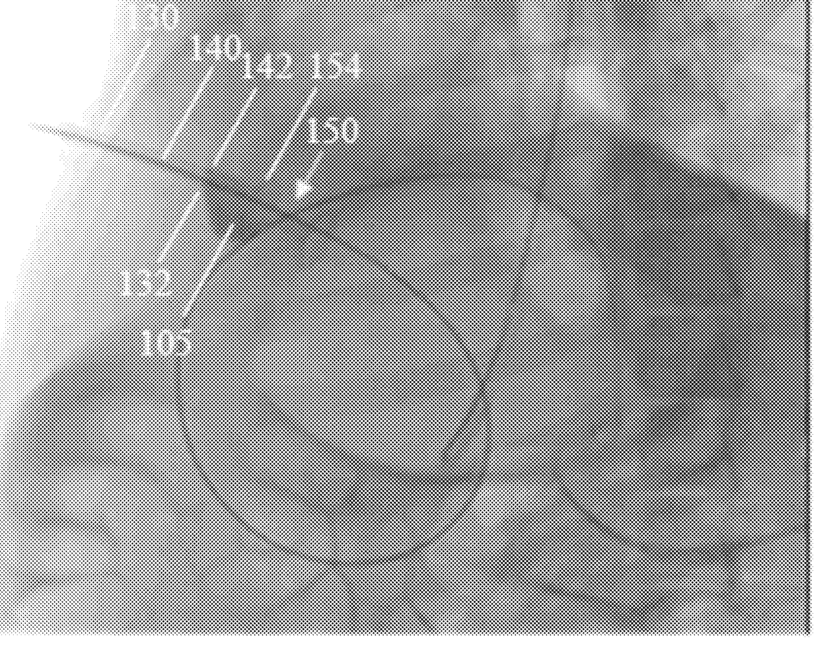

Systems and methods for percutaneous body lumen drainage